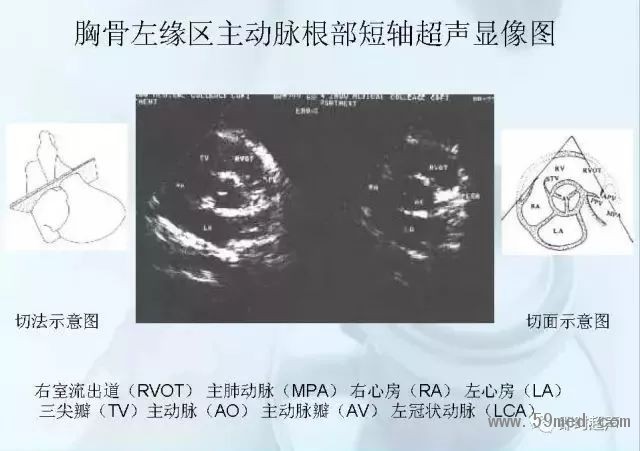

![]() ![]() ![]() ![]() ![]() ![]() ![]() ![]() ![]() ![]() ![]() ![]() ![]() ![]() ![]() ![]() ![]() ![]() ![]() ![]() ![]() ![]() ![]() ![]() ![]() ![]() ![]() ![]() ![]() ![]() ![]() ![]() ![]() ![]() ![]() ![]() ![]() 【注:本文來源于即時超聲,版權(quán)歸原作者所有,如有侵權(quán) 請聯(lián)系 速刪】 =========================== 【閱精彩*悅分享】隨手點擊轉(zhuǎn)至朋友圈,與大家一起分享精彩資訊!當(dāng)然您也可以通過以下方式找到我,與您共同分享藍(lán)韻影像超聲的更多精彩!微信號:landultrasound 電話:+86-0755-66869896 24小時客服熱線:400-888-6452